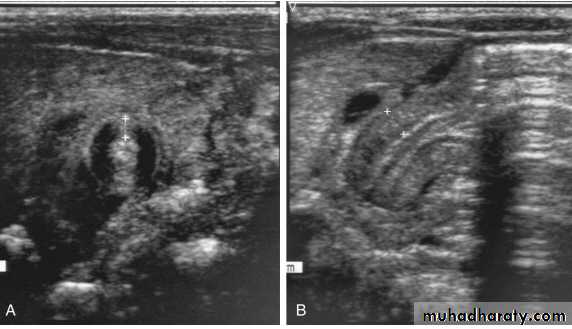

• U/S : confirms Dx in the majority of cases. Criteria include pyloric thickness 3-4 mm, an overall pyloric length 15-19 mm, and pyloric diameter of 10-14 mm. It has a sensitivity of ∼95%.

A, Transverse sonogram demonstrating a pyloric muscle wall thickness of >4 mm (distance between crosses). B, Horizontal image demonstrating a pyloric channel length >14 mm (wall thickness outlined between crosses) in an infant with pyloric stenosis.